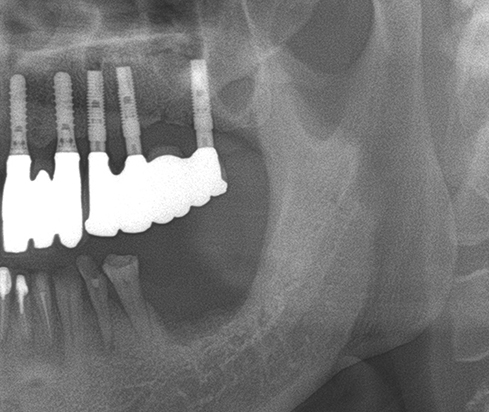

• A clinical case using resorbable membrane 3